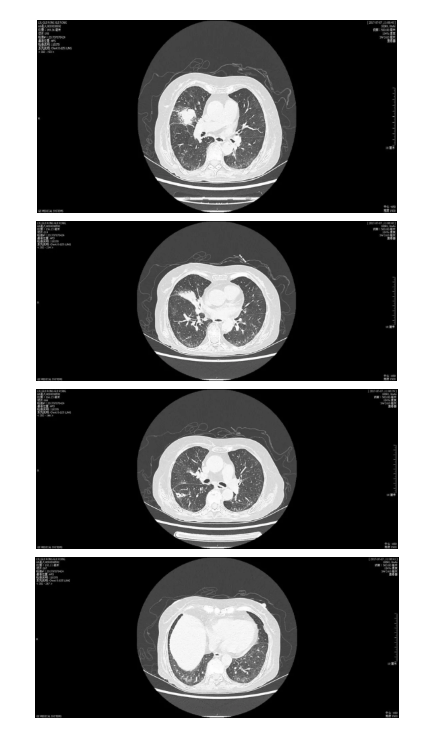

住院期间(2017年7月21日)患者出现咳嗽咯痰加重,伴白细胞升高、呼吸功能衰竭、代谢性酸中毒、电解质紊乱,胸部CT提示左肺下叶新出现渗出影伴双侧胸腔积液。(图1-3)

图1-3 2017年7月23日胸部CT提示原右肺上叶实变影部分吸收,出现小空洞影,左肺下叶新发实变影及斑片影,新发双侧胸腔积液。升级抗生素为碳青霉烯类,并留取痰培养获取病原学资料,7月25日患者痰培养结果为碳青霉烯耐药的肺炎克雷伯菌。予替加环素抗感染。7月26日患者死亡。